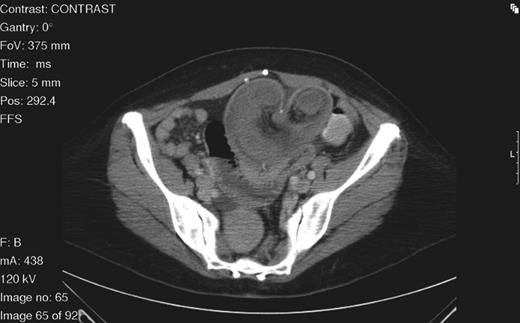

On examination, her abdomen was soft and distended with upper abdominal tenderness. No peritoneal signs were present. An upright abdominal X-ray demonstrated dilated loops of small bowel with air-fluid levels suggestive of SBO. Subsequent contrast-enhanced computed tomography (CT) of the abdomen and pelvis showed dilated loops of small bowel with evidence of strangulation and a mesenteric whirl sign converging at a suture line (Fig. 1).

Axial abdominal CT scan demonstrating a target sign mass consistent with intussusception with its inferior aspect tapering to a point consistent with volvulus.

An emergent laparotomy was performed. Intraoperative assessment revealed an infarcted volvulus segment of small bowel with twisted mesentery and proximal obstruction. The infarcted segment included the jejunojejunostomy suture line, which was resected and reconstructed. The surgical specimen demonstrated intussusception of small bowel with extensive mucosal necrosis. The patient had an unremarkable post-operative course and was discharged to home.